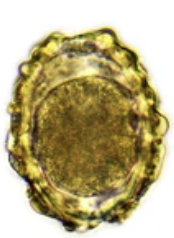

What parasite does this egg belong to?

Ascharis lumbricoides (nematoda)